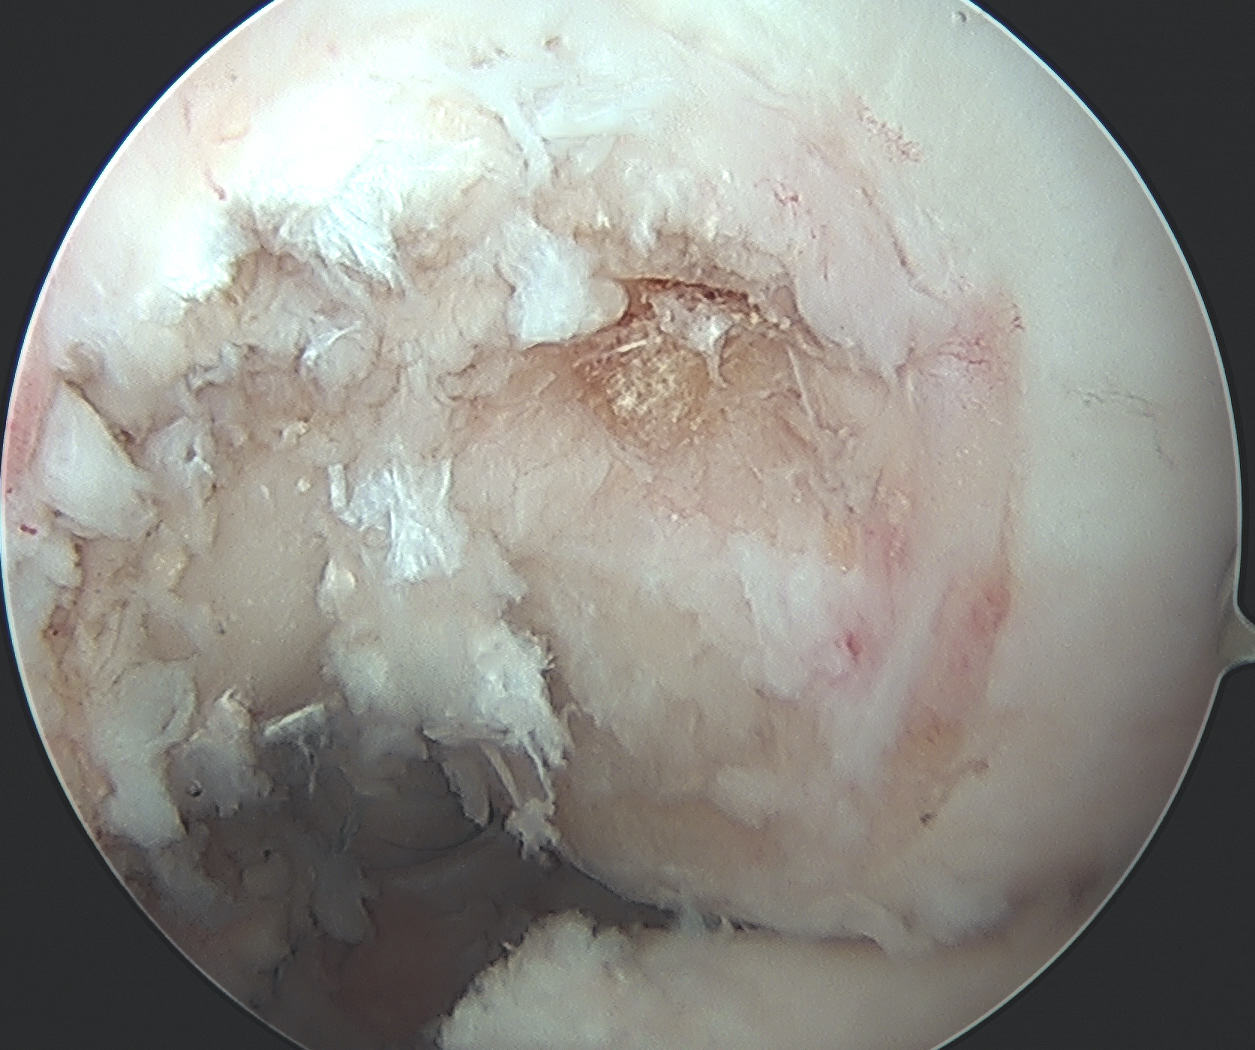

MCL Reconstruction

Femoral side

- use previous proximal medial incision

- identify PCL femoral tunnel

MCL insertion

- identify adductor tubercle (insertion point of adductor magnus tendon)

- medial epicondyle is 12 mm distal and 8 mm anterior to adductor magnus

- insertion point of MCL is 4 mm proximal and 4 mm posterior to medial epicondyle

- can use xray (intersection of the posterior femoral cortex and blumenstaat's line)

Drill MCL femoral tunnel

- 9 x 25 mm

- aim 40o anterior and 40o proximal to avoid PCL tunnel convergence

- insert bony plug and fix with a 7 x 20 mm metal screw